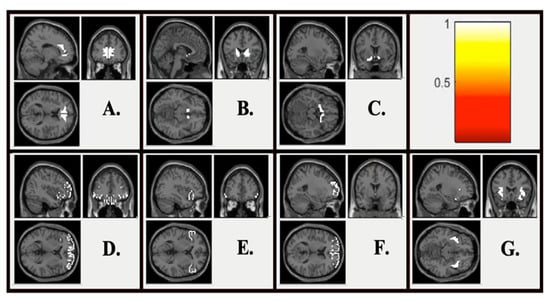

| Seed | Cluster Location | Cluster Size | Coordinates | Statistic | ||

| kE | x | y | z | Z | ||

| Monetary Loss | ||||||

| DS Seed | vmPFC | 112 | +24 | +57 | +12 | 4.47 |

| Insula | 61 | −27 | −12 | +06 | 4.29 | |

| Parietal Operculum Cortex | 55 | −39 | −39 | +18 | 3.90 | |

| mPFC Seed | n.s. | --- | --- | --- | --- | --- |

| Insula Seed | Supramarginal Gyrus | 41 | −60 | −33 | +42 | 4.00 |

| Social Rejection | ||||||

| DS Seed | Cerebellum | 77 | +06 | −84 | −42 | 4.34 |

| mPFC Seed | Central Opercular Cortex | 102 | −57 | −21 | +15 | 5.12 |

| Insula Seed | n.s. | --- | --- | --- | --- | --- |

| Monetary Gain | ||||||

| DS Seed | Parietal Operculum Cortex | 51 | +51 | −21 | +24 | 4.5 |

| Insula Seed | vmPFC | 52 | −24 | +69 | −06 | 3.92 |

| Social Acceptance | ||||||

| DS Seed | n.s. | --- | --- | --- | --- | --- |

| mPFC Seed | Parietal Operculum Cortex | 283 | −51 | −36 | +15 | 4.63 |

| Insula Seed | DS | 53 | −03 | +03 | +06 | 4.88 |